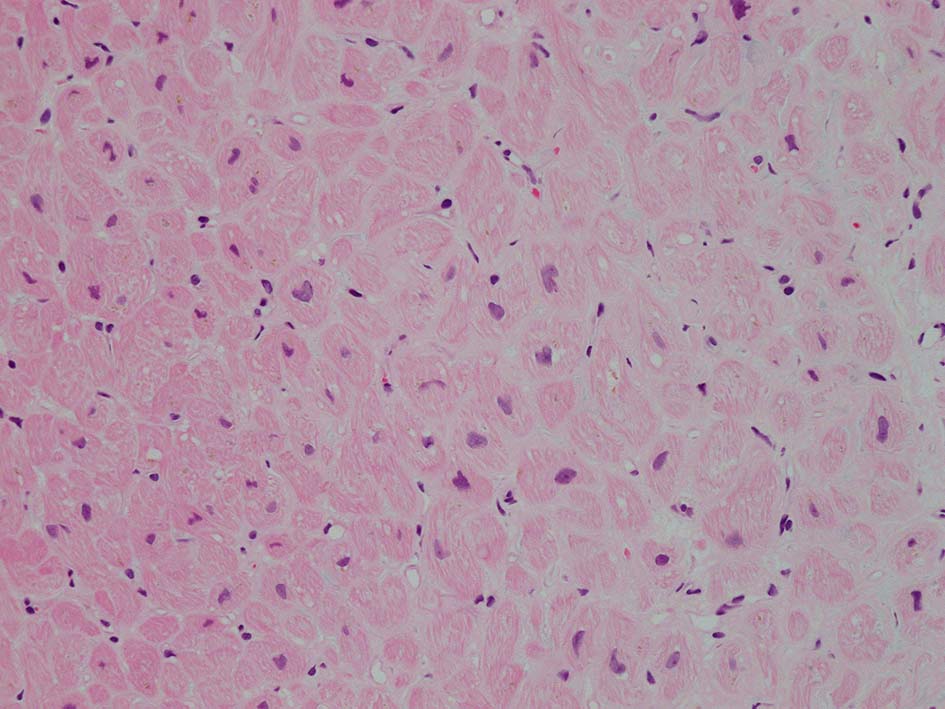

HE所見では, 明瞭な沈着物はわかりにくい. 血管壁が確認できる血管も少ない. congo-red染色で沈着が考えられる所見があり, 簡易偏光で(みずらいけれど)apple-greenの偏光があるように見える.(サムネイルのクリックで大きな画像が見られます)

免疫染色で lambda-LC が陽性に染色されている. kappa-LC, amyloid A, transthyretinは陰性. (免疫染色は浜松医科大学病院病理に依頼し染色していただきました.深謝いたします)